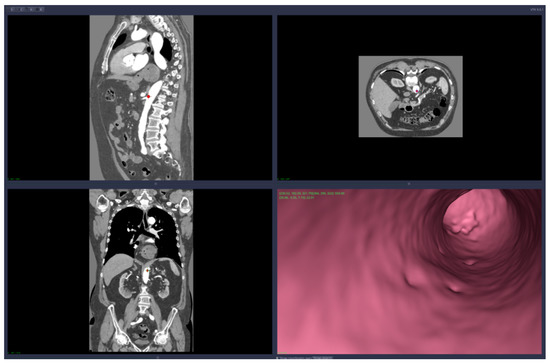

• Virtual angiography—virtual 3D navigation through the mesenteric artery and aneurysm zone (see Figure 3, Figure 4, Figure 5, Figure 6 and Figure 7)

The CardioCTNav software platform was able to distinguish between the zones that were both inside and outside the arteries and to detect the artery walls. Target points can be chosen by the user interacting with the 2D sections; they are colored according to the zone where they are placed (outside or inside the artery). The platform is also able to detect an “inside” zone closest to a point that is initially placed in an “outside” zone.

Virtual angiography means that the user is able to navigate inside the artery using only the computer mouse device. The navigation starts from a point chosen by the user and the virtual camera is forced to remain inside the artery walls. The algorithm that implements this restriction on the virtual camera is based on collision detection and resolution directly on voxels (no segmentation is required). The path of the virtual angiography can be saved and used later, in other planning sessions.

Figure 3. Virtual angiography—“normal” zone of the mesenteric artery, before the aneurysm (direction is opposite to the blood flow).

Applsci 11 10311 g003

Figure 4. Virtual angiography—inside the mesenteric artery aneurysm (direction is opposite to the blood flow).

Applsci 11 10311 g004